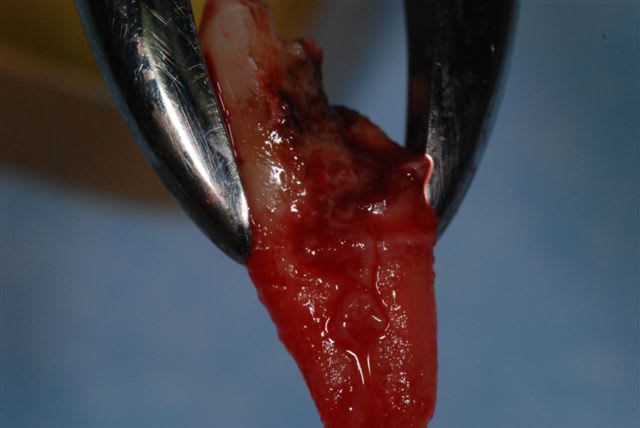

suite de la prémolaire fracturée: extraction , mise en place d'un implant tekka diametre 4 longueur 15 mm pour aller chercher un bon ancrage primaire. Il y avait 2 mm d'espaceentre l'implant et la corticale en vestibulaire et 1 mm en palatin, j'ai comblé au bio-oss et tracté la muqueuse sans tensions pour le recouvrir.

pas de photos du bio-oss en place car assistante absente et donc galère pour prendre la photo à ce stade.